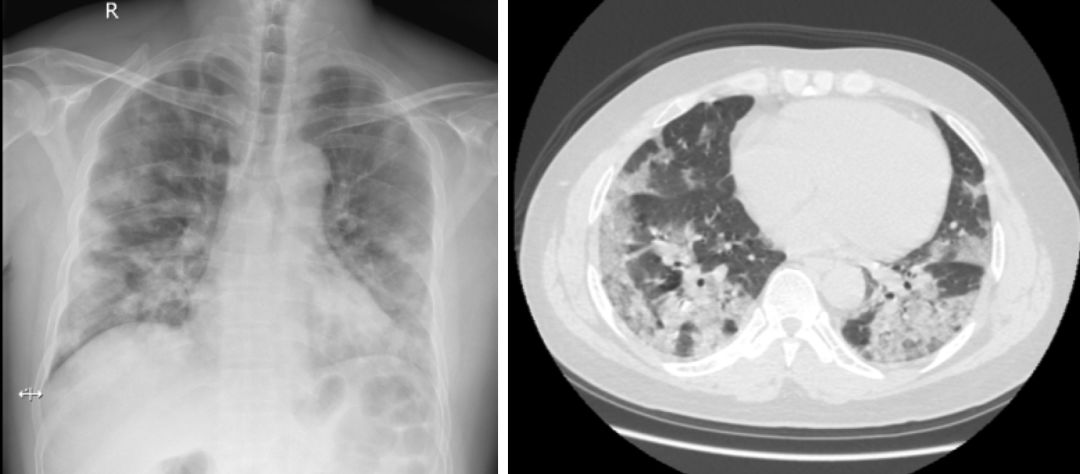

由流感病毒感染本身引起的肺炎,称为单纯性流感病毒肺炎 [7]。通常在2~3天典型的流感症状之后,全身状态急剧恶化,伴有明显的呼吸困难和气短。大多数患者出现低氧血症,可进展为严重的急性呼吸窘迫综合症(ARDS)[8]。外周血白细胞和淋巴细胞计数减少,痰培养不能发现有意义的致病菌。胸部X线特征性的改变是肺部出现磨玻璃样、线状或网状等间质性阴影,可累及双肺(图1);一般没有所谓的浸润或实变影,也不会出现空洞 [9]。组织病理表现为弥漫性肺泡损伤(DAD),极少数的患者可以表现为闭塞性细支气管伴机化性肺炎(BOOP),此时可出现胸膜下的肺部实变(图2)。

(图1、图2)